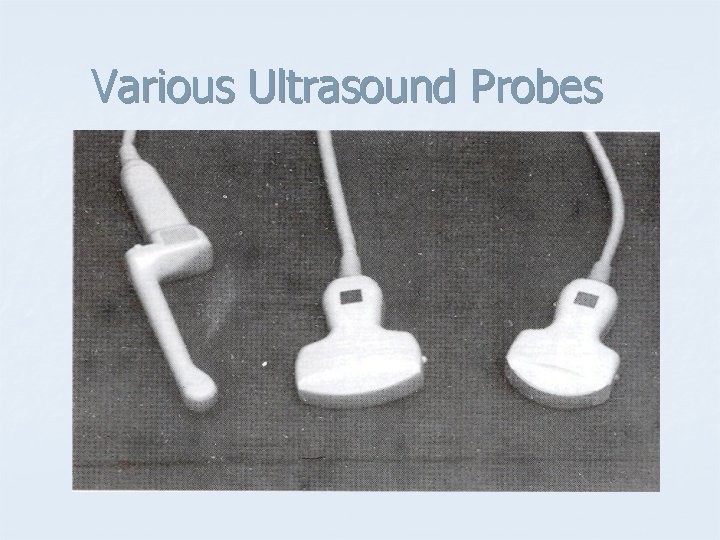

Various Ultrasound Probes